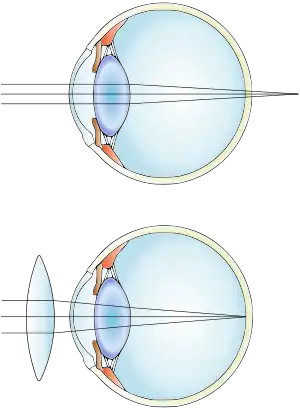

| Far-sightedness without (top) and with lens correction (bottom) | |

Far-sightedness, also known as hypermetropia, is a condition of the eye in which light is focused behind, instead of on, the retina.[2] This results in close objects appearing blurry, while far objects may appear normal.[2] As the condition worsens, objects at all distances may be blurry.[2] Other symptoms may include headaches and eye strain.[2] People may also experience accommodative dysfunction, binocular dysfunction, amblyopia, and strabismus.[3]

The cause is an imperfection of the eyes.[2] Often it occurs when the eyeball is too short, or the lens or cornea is misshapen.[2] Risk factors include a family history of the condition, diabetes, certain medications, and tumors around the eye.[2][4] It is a type of refractive error.[2] Diagnosis is based on an eye exam.[2]

The simplest form of treatment for far-sightedness is the use of corrective lenses, eyeglasses or contact lenses.[15][16] Eyeglasses used to correct far-sightedness have convex lenses.[17]